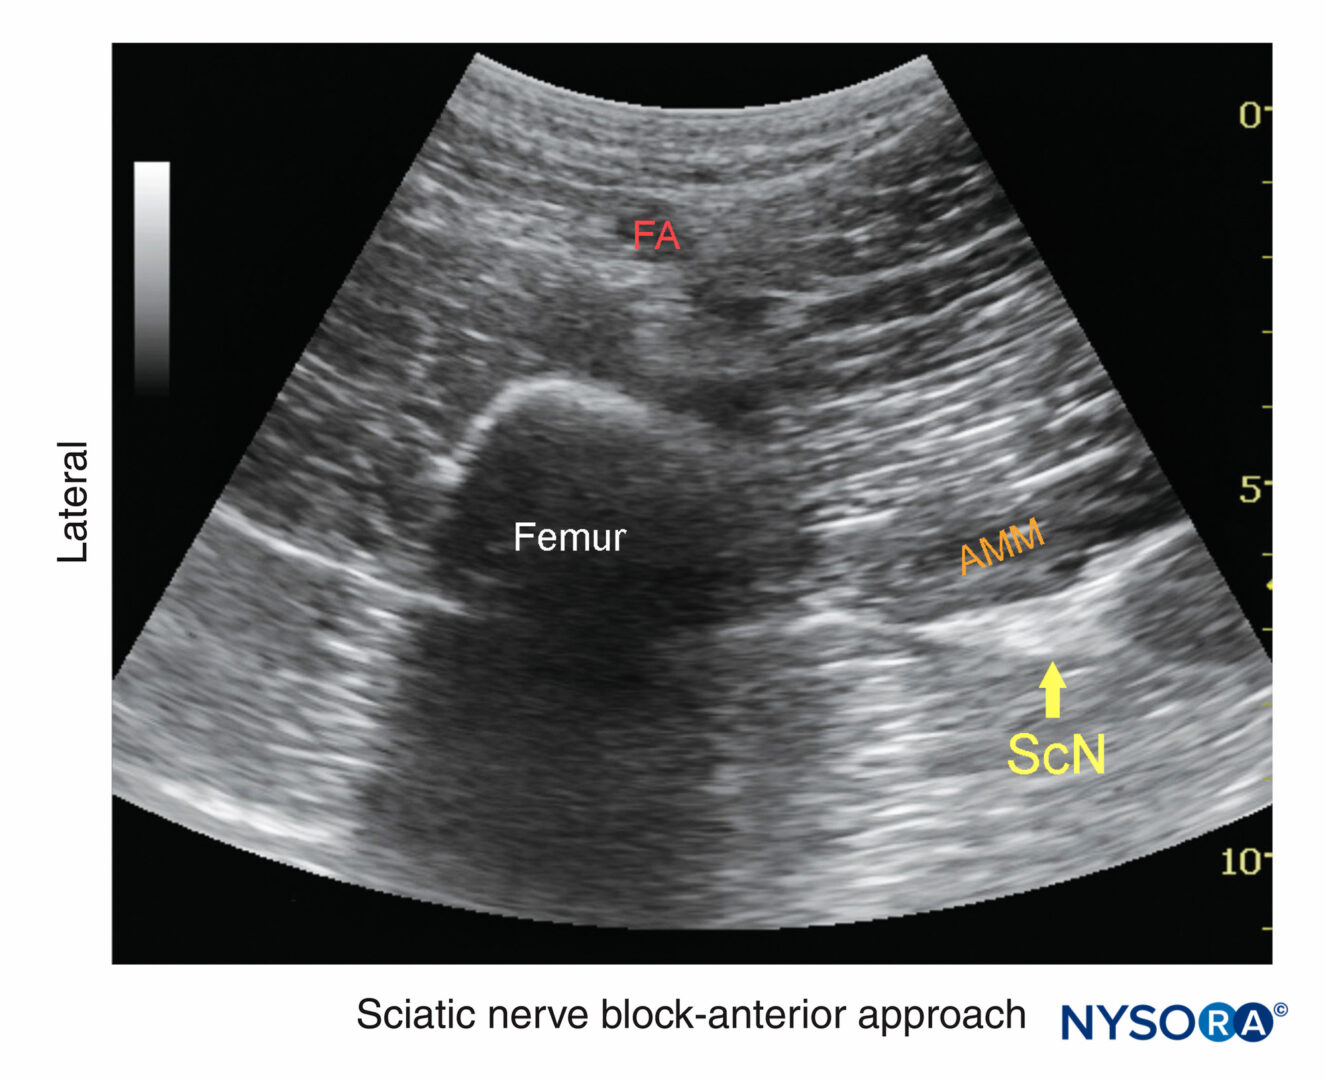

From www.nysora.com

regionalanesthesiasciaticnerveblockanteriorapproach NYSORA NYSORA Anesthesia Nerve Block Procedure The injection can be close to the spine itself or on the abdomen itself. If you are planning to have surgery and you’ve never had (or heard of) a nerve block, a type of regional anesthesia, you might be surprised to learn how easy and effective it is. A nerve block is the injection of numbing medication (local anesthetic) near. Anesthesia Nerve Block Procedure.